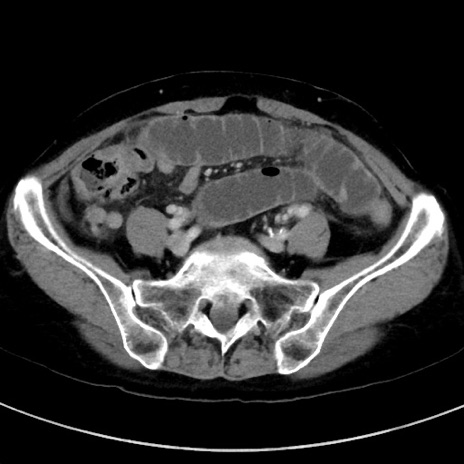

症例23(横断像)

【症例】70歳代女性

【主訴】下腹部痛・嘔吐

【現病歴】2日前より腹痛あり。昨日嘔吐あり。症状改善しないため来院。

【既往歴】胃GISTに対して胃部分切除後。

【身体所見】BT 37.1℃、BP 128/77mmHg、腹部:平坦・軟、下腹部に圧痛あり。

【データ】WBC 10200、CRP 0.31